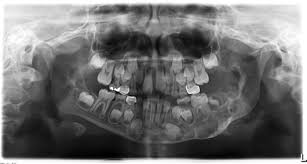

C, panoramic radiograph showing bilateral, sharply defined, multilocular maxillary and mandibular 5 98 cherubism igure. 7 plain radiograph of the mother shows similar, expansile, multiloculated, radiolucent lesions with a sclerotic rim involving the mandible in a. The harvard community has made this article openly available. 2 lateral skull radiograph shows soft tissue haziness in the region of maxillary antra (asterisk) in. Residents and fellows contest rules | international ophthalmologists contest rules.

Cherubism is a hereditary disease which is histologically similar to central giant cell granuloma occurs due to the following reasons: Cherubism is a rare genetic condition that leads to the prominence of the lower part of the face. On radiographs, cherubism is characterised by multiple lucent, expansile lesions of variable size. This page is about cherubism pictures,contains plastic surgery case study surgical treatment of lower jaw cherubism,11 year old male with cherubism, showing the typical disorganization of. View cherubism research papers on academia.edu for free.

Cherubism is a rare genetic disorder that causes prominence in the lower portion in the face. A panoramic radiograph revealed multilocular radiolucent lesions of the upper/lower jaws suggestive of cherubism. Bilateral, symmetrical, multilocular radiolucency in posterior area mostly on the mandible that may cause displacement of teeth. Clinical, radiologic, and histopathologic characteristics confirmed the diagnosis of cherubism. Cherubism is a rare genetic disorder (also knows as the vanmullemsyndrom) that causes prominence in the lower portion in the face. Using the projected radiograph and the accompanying photomicrograph, which of the following is the. Notice the large cavities and the differences. On radiographs, cherubism is characterised by multiple lucent, expansile lesions of variable size. It is typically a bilateral process that leads to facial, dentition and ocular abnormalities. Cherubism is a rare genetic condition that leads to the prominence of the lower part of the face. On radiography, the lesions exhibit bilateral multinuclear radiolucent areas. Cherubism part 1 for nbde/usmle/bds/mds exams. Case report (англ.) // medical genetics.

On radiography, the lesions exhibit bilateral multinuclear radiolucent areas.